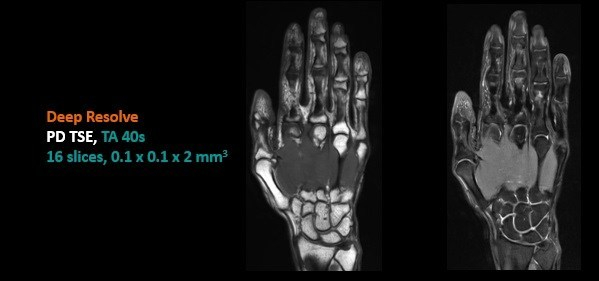

Deep Resolve实现手部100um超高分辨率成像,将MR影像提高到空前水平